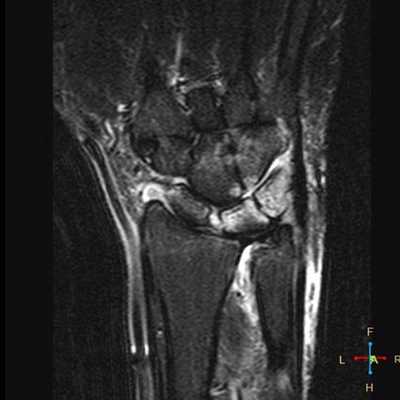

Ревматоидный артрит. Субхондральные эрозии, гипертрофия синовиальной оболочки.

Ревматоидный артрит. Анкилозирование костей запястья, деструкция эпифизов лучевой и локтевой костей.